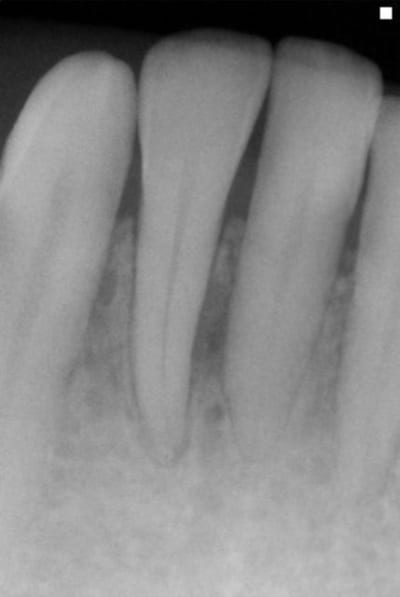

ce cas me remet en mémoire un article de charon: "le fibroblaste est- il radio opaque?"

pca patient 45 ans

flore incompatible, batonnet et spirochètes

abcès vestibulaire 42

birodogyl et séances de lithotritie+ soins locaux désinfection de juin à novembre avec irrigation bétadine

zône non sondées jusqu'à guérison radio

il y a encore un an , j'aurais été très dubitatif sur l'avenir de cette dent. Maintenant, j'y regarderai à deux fois avant de porter un jugement hatif........car les fibroblastes ne sont pas radio opaques!

ces radio se voulaient juste une interpéllation sur des résultats spectaculaires.

Personnellement, j'ai trouvé un résultat au delà de mes attentes alors qu'une régénération osseuse au niveau d'une lésion endo ne me surprend pas ou bcp moins.

Je ne crois pas que le laser ou la litho(inserts paro sur détartreurs soniques ou ultrasoniques)soient pour grand-chose dans le résultat présent : aucune spicule de tartre visible.

Sur la première radio il semble bien qu'il reste une partie du septum, donc tu donnes des AB pour éviter une perte osseuse supplémentaire mais les soins locaux prennent le relais.

J'étais plus intervenu depuis longtemps parcequ'on m'avait dans les hautes sphères d'eugénol,demandé de me calmer,mais je peux pas laisser passer ça.On est dans un cas typique de guérison à la Sainte Carole, priez pour nous.La radio de départ elle est pourrie de chez pourrie.Comment on peut faire un diagnostic dans ces conditions?Comment on peut affirmer qu'il y a eu guérison, s'il n'y avait pas de lésion au départ.C'est absolument n'importe quoi.Il suffit de passer ces deux images à photoshop pour se rendre compte que les niveaux ne correspondent pas,et que sur la première image on est surexposé,ce qui brûle obligatoirement certaines zones de l'image,et que sur la deuxième on est sous exposé.Dans ces conditions,c'est ni six mois,ni trois,ni un jour,c'est en une seconde que je vous obtiens autant de guérisons miraculeuses que vous voulez.Y a vraiment personne qui réfléchit ici avec sa tête au lieu de s'extasier sur rien?pierres,va faire un stage de prise de radio avant de penser que tu es devenu un parodontiste émerite.

Meme si tu n y met pas les formes ta raison, sur la premiere radio on voit un defaut oseux evident masi on remarque aussi le sommet du septum interdentaire ... La preuve que la radio a été sur exposée

la différence d'exposition entre les deux clichés est évidente aussi, et c'est un défaut de la présentation.

Ceci dit , cela rend intéressant à postériori l'usage des réglages contrastes pour visualiser l'os à perdre ou à regagner. Le numérique nous le permet. La question étant y a t il encore une trame ou plus rien.